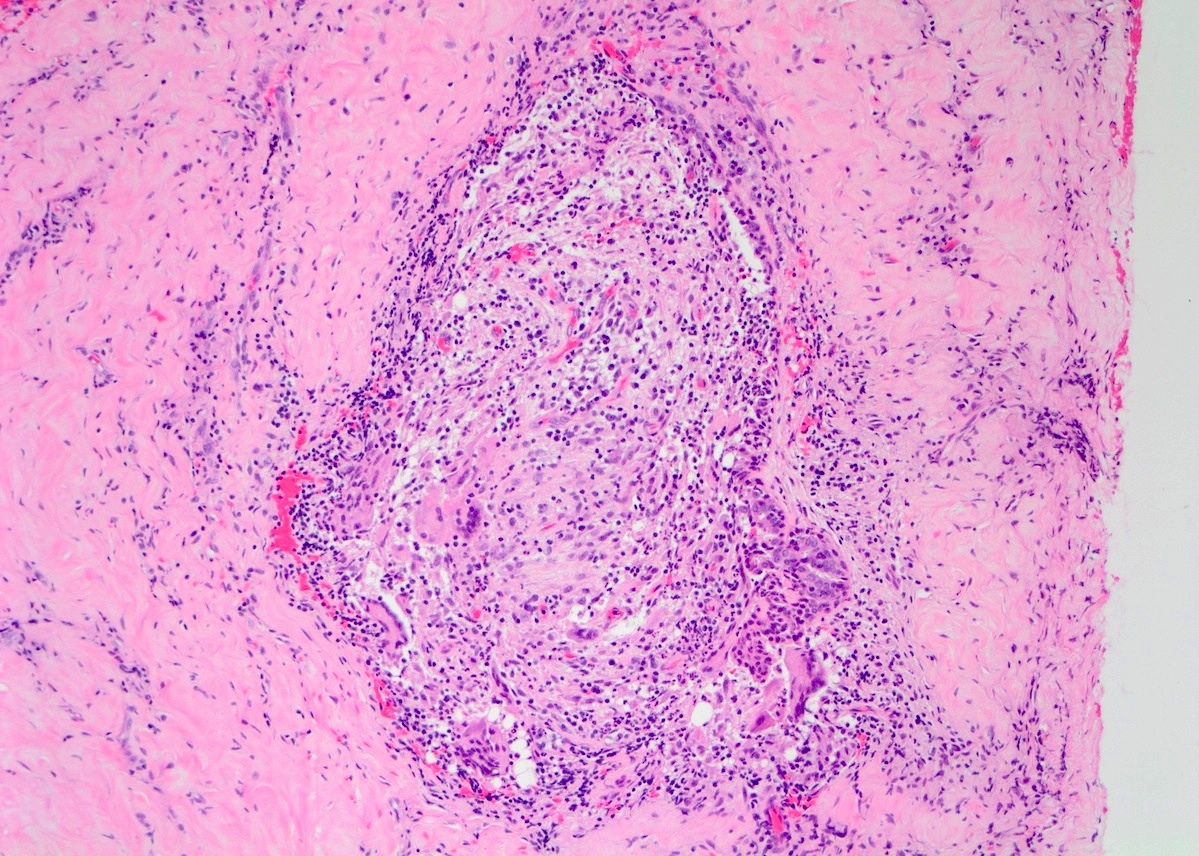

Microscopic (histologic) description

- Lobulocentric granulomatous inflammation (Pathology 2004;36:254)

- Granulomas often contain neutrophils

- Neutrophils can create microabscesses; overlapping features with cystic neutrophilic granulomatous mastitis

- Multinucleated giant cells, lymphocytes, plasma cells and eosinophils within and around lobules

- Extensive inflammation might obliterate lobulocentric distribution

- Caseous necrosis not present

- Schauman and asteroid bodies not common

Microscopic (histologic) images